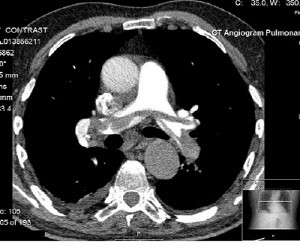

CT 사진의 원리

CT 사진의 원리가 누리꾼들의 궁금증을 자아내고 있다.

최근 한 포털사이트 게시판에는 CT 사진의 원리에 대한 게시물이 올라왔다. 공개된 게시물에 따르면 계산이 빠른 컴퓨터가 등장 한 후 CT가 실용화되는데 결정적인 역할을 한 것은 이산 푸리의 변환을 빠른 시간내에 계산하는 방법이다.

이는 컴퓨터에도 이식하기 좋은 계산법인 고속 푸리에 변환(FFT, Fast Fourier Transform)이 나오면서부터이다.

푸리에 변환은 공학이나 물리학 등에서 광범위하게 등장하는 변환으로, 푸리에 변환의 역변환은 적분을 통해 얻는다.